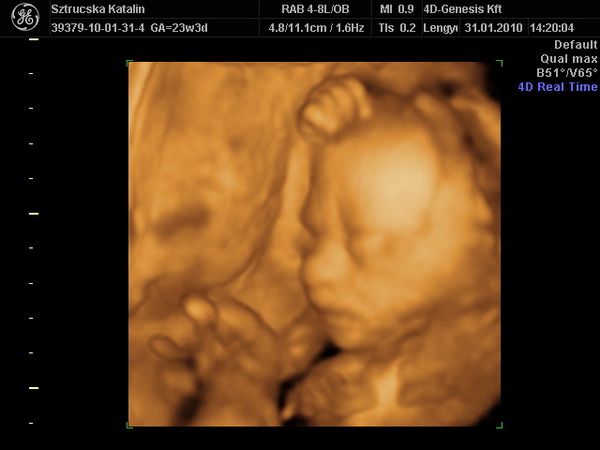

Tök jó, hogy ilyen szép nagyok a csajok! Holnap mindenképp megtippeltetem magunkat is Apánkkal. Már nekem is fúrja az oldalam a kíváncsiság. A mi fejünk sem volt túl nagy a múltkor...de már a 4D-n is úgy volt, hogy az oldalsó átmérő kisebb volt, elölről hátra nagyobb (tehát oldalról kicsit lapított a búránk) de így a körméret meg pont megfelelő lett. Pedig a képen milyen kis holdvilág képe van Nimókának.